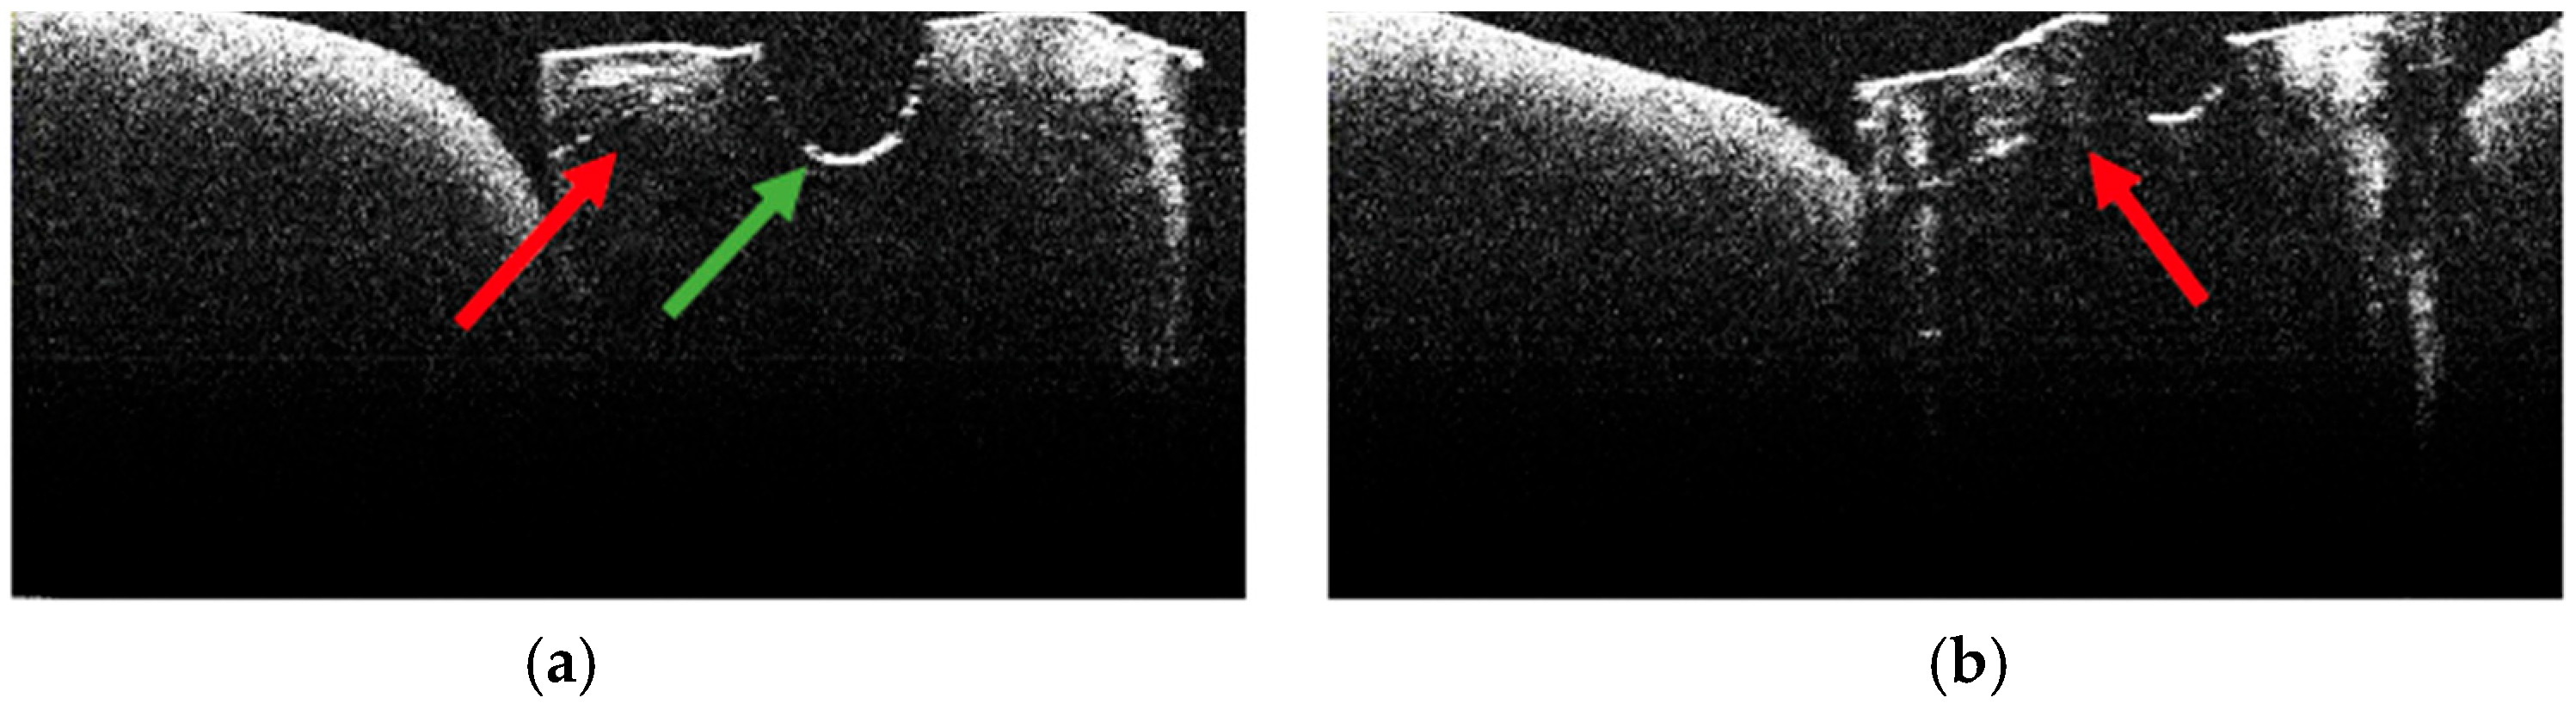

3.2. Defining OCT Signatures: Alterations vs. Artefacts

3.5. OCT Examination of Specimens from Group B